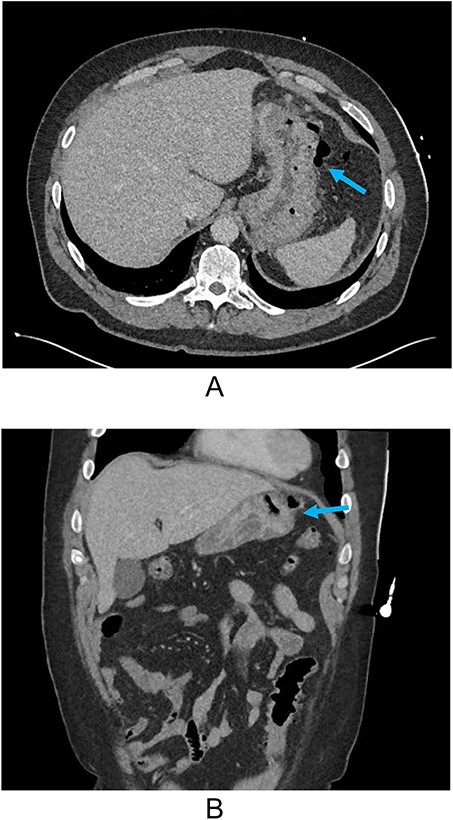

He was hypertensive on arrival (176/115 mmHg) but had otherwise normal vital signs. Abdominal examination yielded focal peritonism in the epigastrium and left upper quadrant and erect chest x-ray demonstrated free air. His initial blood results were only significant for a mild compensated metabolic acidosis and mildly elevated white cell count (11.9×109/L, RR 4–11). His subsequent CT showed free intra-peritoneal air predominately in the upper abdomen with a penetrating ulcer on the greater region of the gastric body (Fig. 1A and B).

(A) Axial CT and (B) coronal reconstruction demonstrating perforated gastric ulcer at the greater region of the gastric body (arrows).